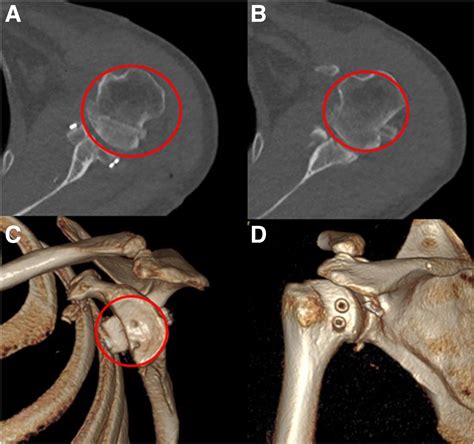

To accurately identify the extent of a Hills Sachs lesion, orthopedic specialists use various imaging techniques. A standard physical examination usually includes provocation tests to check for joint laxity, but the definitive diagnosis relies on high-quality medical imaging:

CT Scan The gold standard for quantifying the amount of bone loss in the humeral head and glenoid.

💡 Note: While a CT scan is highly accurate for bony defects, a surgeon will almost always order an MRI to assess associated soft tissue injuries like a Bankart tear, which frequently accompanies a Hill-Sachs lesion.